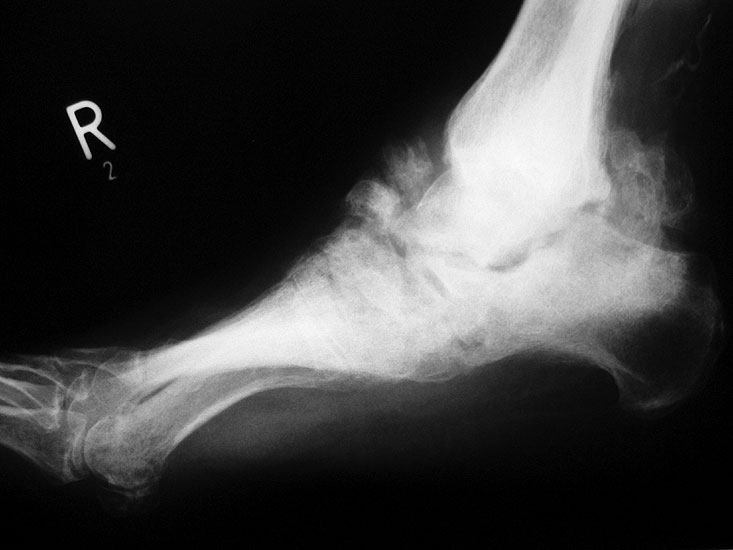

Abbildung 3

DNOAP Typ II (Abb. 3)

Typ II der DNOAP betrifft die Tarsometatarsalgelenke. Hierbei kommt es zur Ausbildung eines hochgradigen Plattfußes durch Luxation der Ossa cuneiformia und/oder naviculare. Typische Folge ist eine ausgeprägte Vorfußabduktion. Durch die hohe Druckbelastung im cuneiforme-naviculare Bezirk sind plantare Ulcerationen häufige Folge.